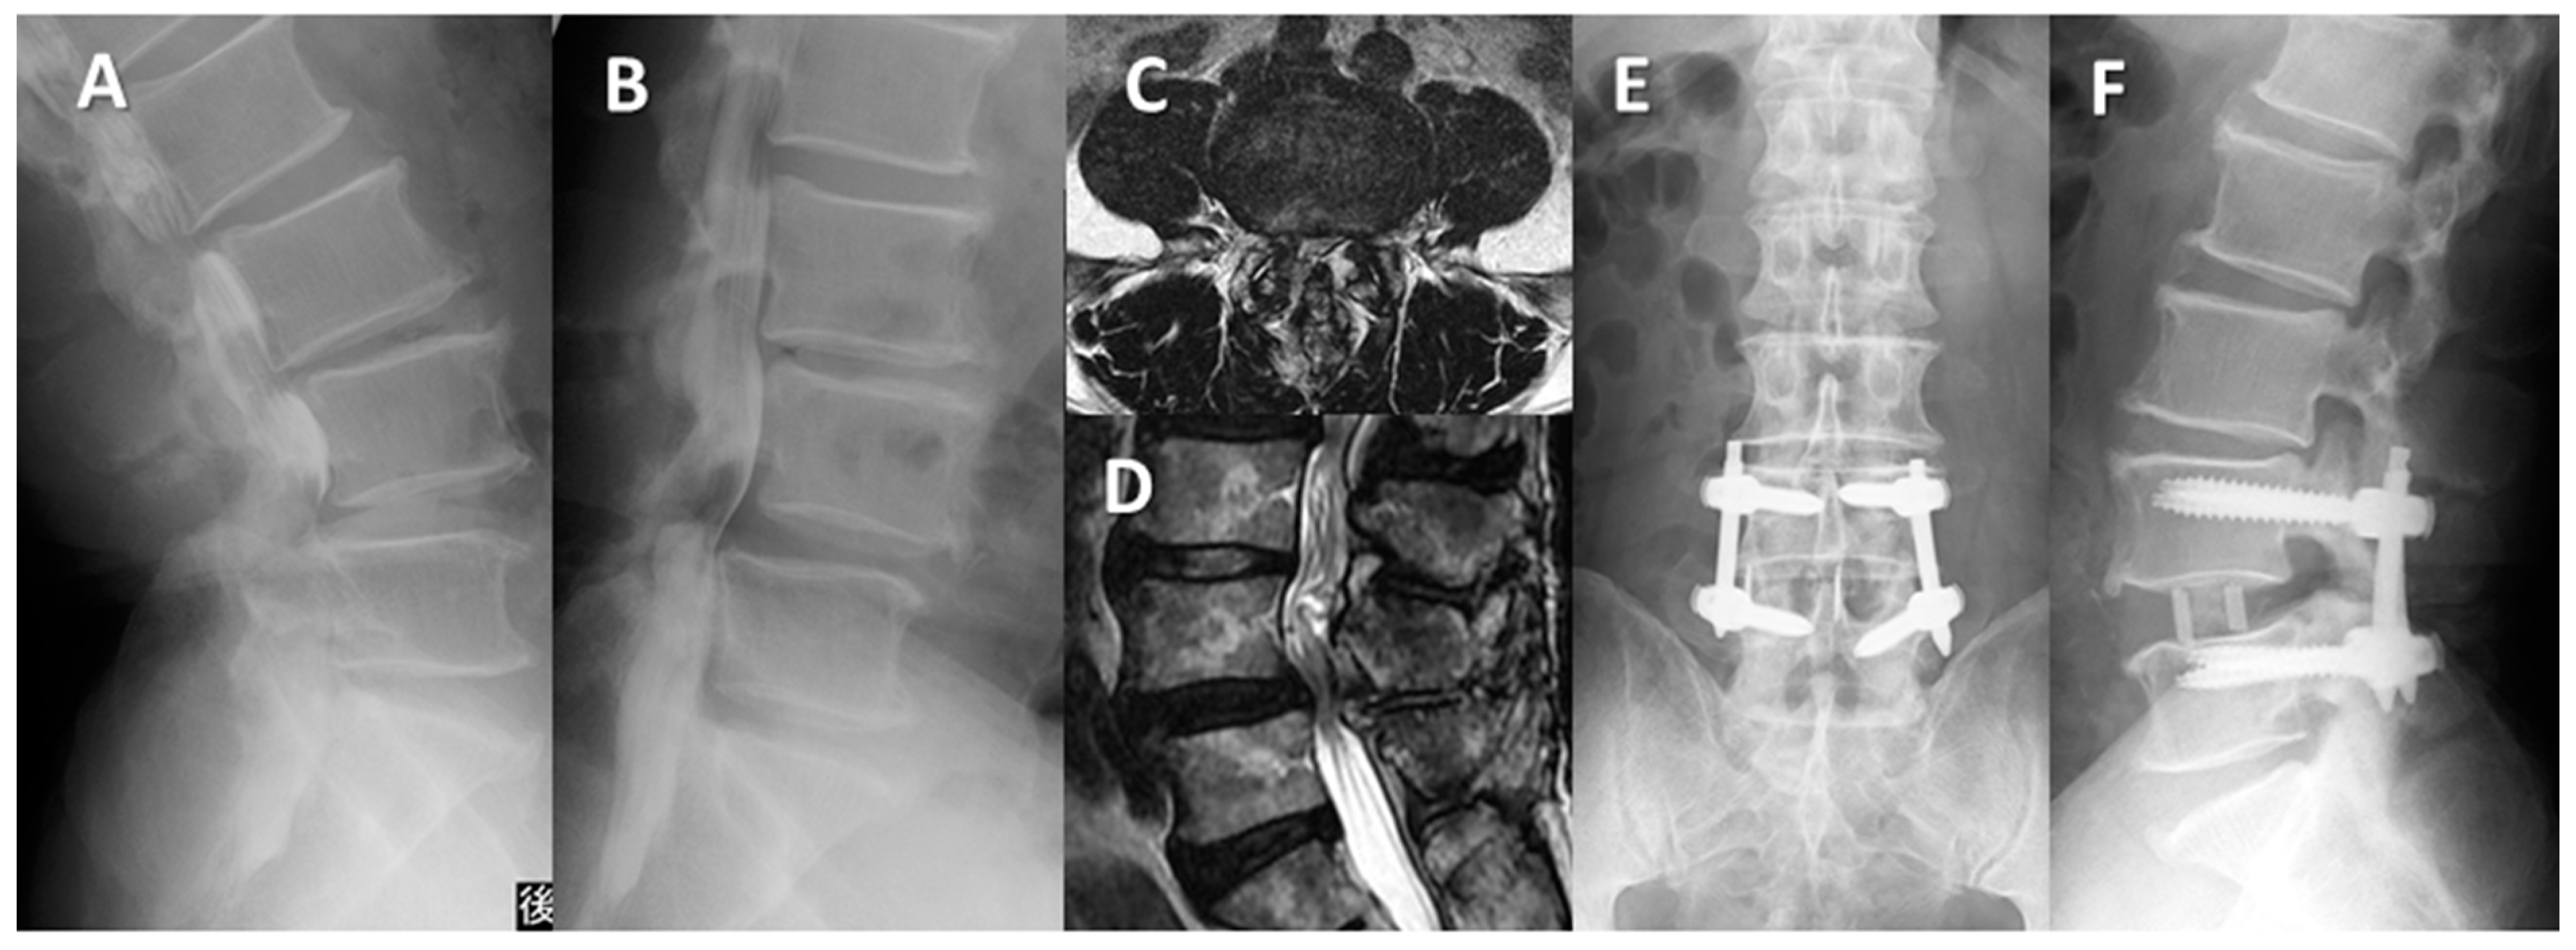

Case Presentations